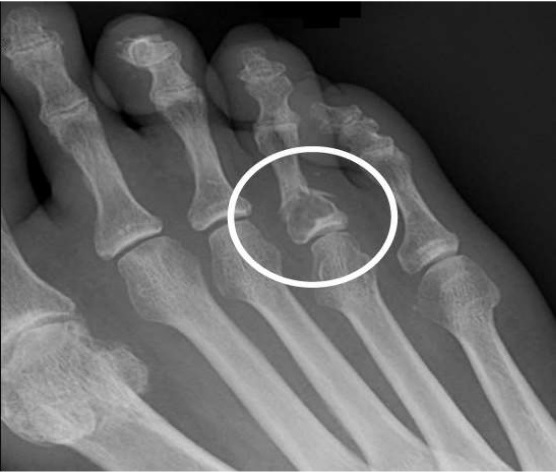

Similar to Non-ossifying Fibroma, Fibrous Cortical defect is usually asymptomatic. Many children and adolescents often do not even know that they have this defect present in their bones. This defect is discovered or diagnosed in a child or youngster incidentally through an X-ray for any other purpose. But some people who have experienced this disease reported the following symptoms.

- X-rays help in producing clear and sharp images of bones.